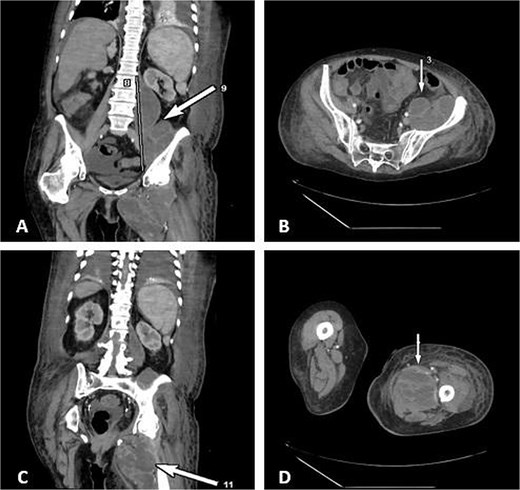

Contrast-enhanced CT demonstrated a large multiloculated IPA extending distally along the psoas sheath into the upper thigh, involving the adductor compartment (Fig. 1).

CT demonstrates multiloculated IPA with distal extension into the thigh adductor compartment. (A) Coronal CT showing a multiloculated IPA. (B) Axial CT demonstrating the psoas collection. (C) Coronal CT illustrating distal extension along the psoas sheath into the adductor compartment. (D) Axial CT of the thigh confirming distal involvement.